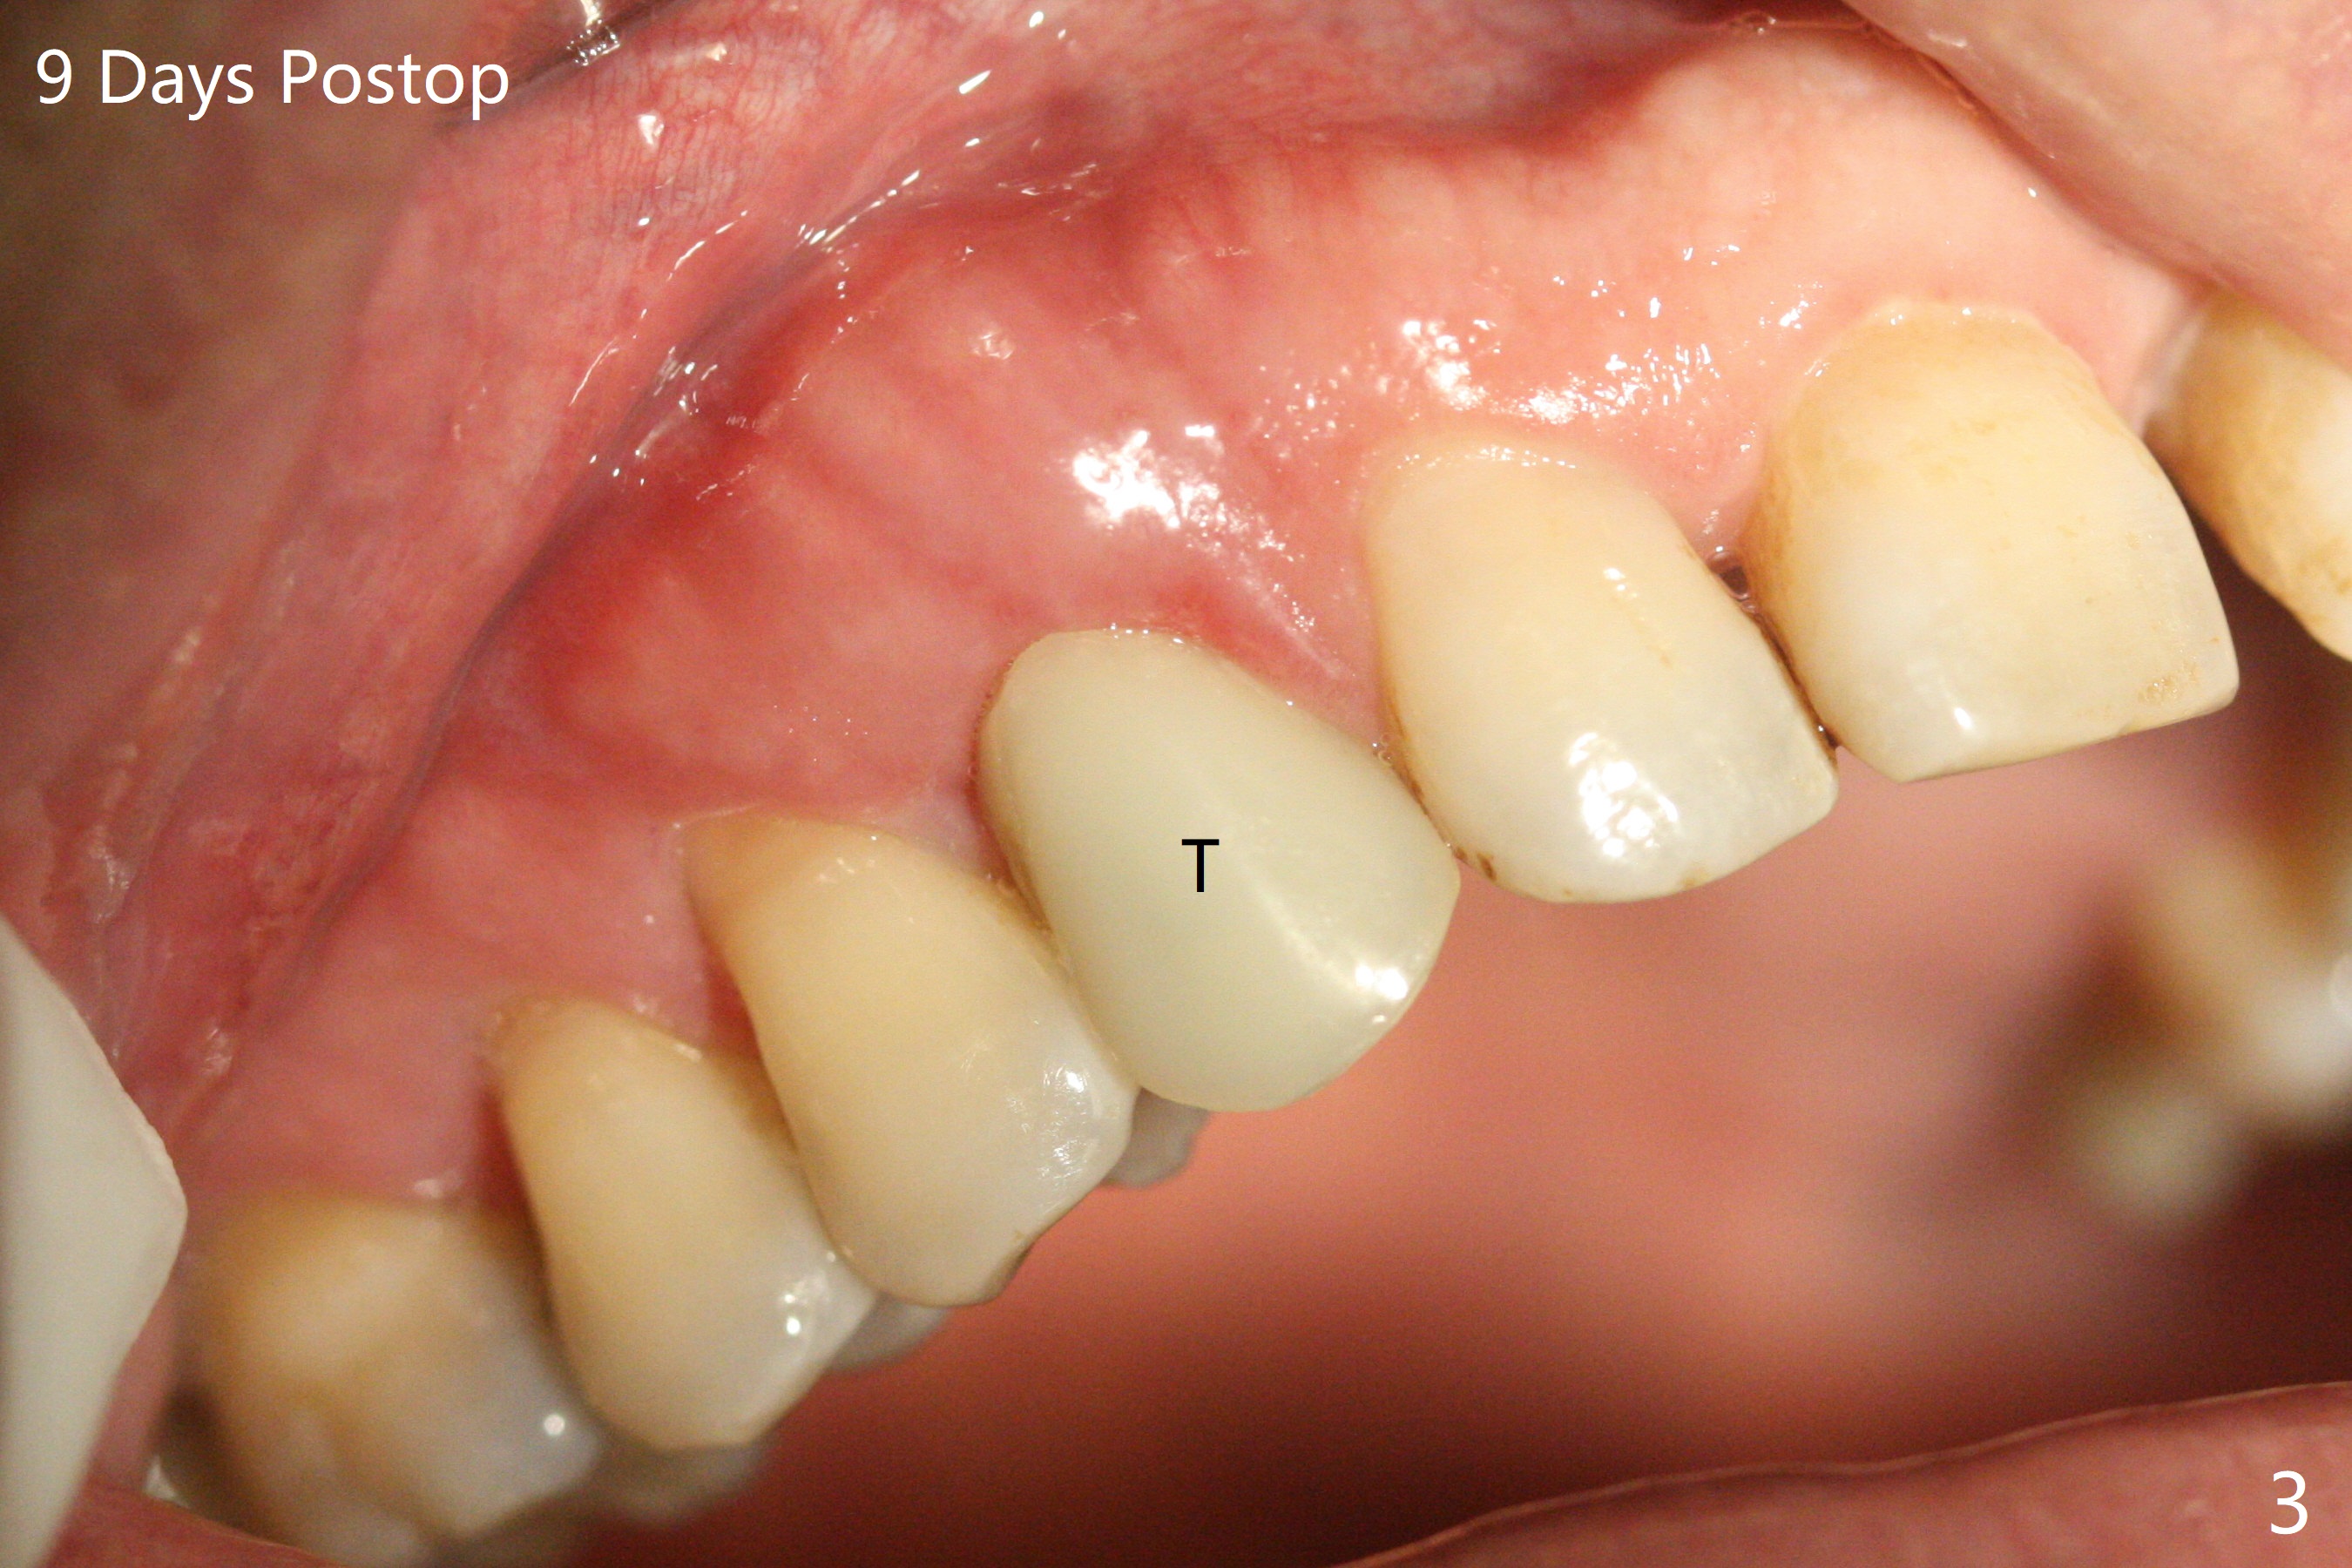

右上乳尖牙拔除后,颊侧尖牙隆起仍旧明显(图一:*(牙槽窝塞入止血纱布)),希望通过导板即种和植入粘性骨粉(图二:*)以及即修,这个局部解剖结构能保留下来。至少术后9天是这样(图三,T: 临时牙冠)。Return to Protect Graft Xin Wei, DDS, PhD, MS 1st edition 05/27/2021, last revision 06/05/2021